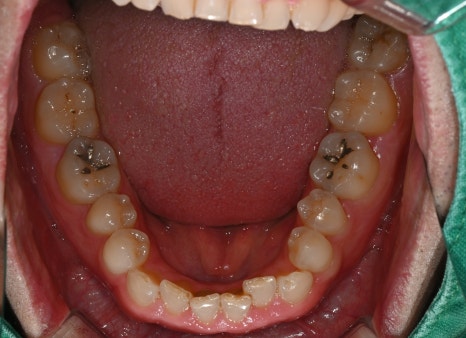

Third photo: Lower molar photo taken at the initial visit. Caries had progressed in two lower molars, and inlay treatment was needed.